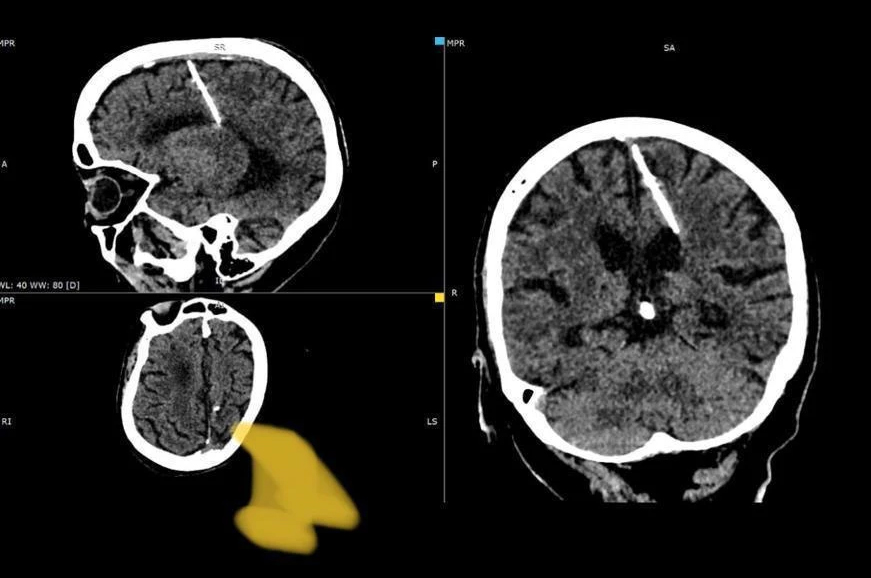

عثر أطباء خلال فحص بالتصوير المقطعي على إبرة بطول ثلاثة سنتيمترات موجودة منذ 80 عاما داخل دماغ امرأة مسنة في أقصى الشرق الروسي.

وقالت إدارة الصحة المحلية "لقد اخترقت الإبرة الفص الجداري الأيسر، لكن لم يكن لها التأثير المقصود، إذ نجت الفتاة".